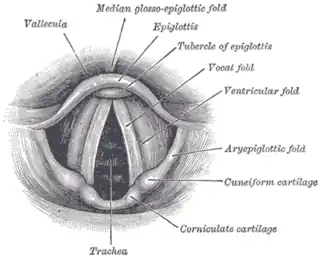

Laryngoscopic view of the vocal folds. | |

In humans, the vocal cords, also known as vocal folds, are folds of throat tissues that are key in creating sounds through vocalization. The length of the vocal cords affects the pitch of voice, similar to a violin string. Open when breathing and vibrating for speech or singing, the folds are controlled via the recurrent laryngeal branch of the vagus nerve. They are composed of twin infoldings of mucous membrane stretched horizontally, from back to front, across the larynx. They vibrate, modulating the flow of air being expelled from the lungs during phonation.[1]

The vocal folds are located within the larynx at the top of the trachea. They are attached at the back to the arytenoid cartilages, and at the front to the thyroid cartilage via Broyles ligament. They are part of the glottis. Their outer edges are attached to muscle in the larynx while their inner edges form an opening called the rima glottidis. They are constructed from epithelium, but they have a few muscle-fibres in them, namely the vocalis muscle which tightens the front part of the ligament near to the thyroid cartilage. They are flat triangular bands and are pearly white in color. Above both sides of the glottis are the two vestibular folds or false vocal folds which have a small sac between them.